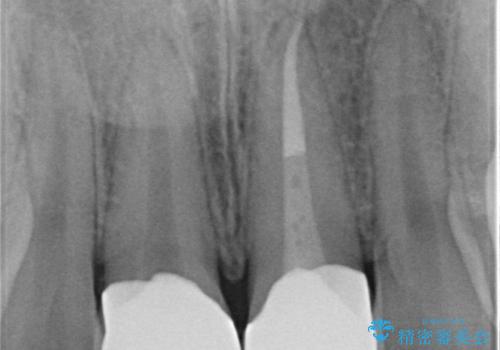

- 前歯を良くしたい(綺麗にしたい)との事で来院。

前歯のがたつきを治す治療プランとして

1 矯正を行い歯並びを良くする。(費用と時間がかかる)

2 セラミッククラウンで見た目を良くする(短時間で終わるが歯の向きを無理やり変えるために便宜的に歯の神経を抜く必要がある。健康な歯を削る)

のご提案をしたところ2のプランを選択されたのでセラミック治療を行いました。

- ジルコニアクラウンスペシャル・仮歯 16.5万円×2 精密根管治療(イニシャルトリートメント)・ファイバーコア 8.8万円費用は治療当時の料金となります

根管治療の注意事項(リスク・副作用など)

- 根管治療により類似の全ての症例の問題が解決するわけではなく、症例はあくまでも一例です

- 根管治療により痛みや腫れがひかない事や、術後に痛みや腫れが生じる事、治療によるファイル破折やパーフォレーションなどの偶発症、術後の歯根破折を生じる可能性もあります

- 自費診療(保険適用外)となります